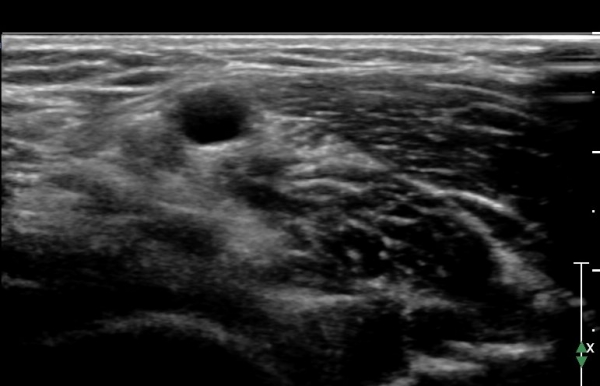

Á¤Á߽Űæ Á¾´Ü¸é°Ë»ç¿¡¼ ȸ³»±Ù ¿ä°ñµÎ ±â½ÃºÎ¿¡¼ Á¤Á߽ŰæÀÇ ±¹¼ÒÀû ¾Ð¹Ú°ú Ç¥ÃþÀ¸·Î ÀüÀ§°¡ °üÂûµÇ°í ¾Ð¹ÚÀÇ ±ÙÀ§ºÎ¿¡¼´Â Á¤Áß½Å°æ ºÎÁ¾ÀÌ °üÂûµÊ(»çÁö 3). ÀÌ·± º¯È´Â °ÇÃø(»çÁø 6)°ú ºñ±³ÇÏ¸ç ¶Ñ·ÇÇÔ.